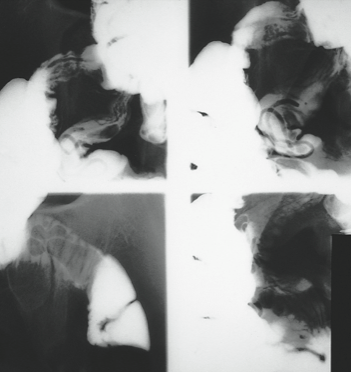

A 30-year-old woman had had no medical problems until she suffered a 4-week bout of coughing, wheezing, and fever while traveling in Indonesia. This was followed by diarrhea, nausea, vomiting, abdominal pain in the right upper quadrant, and anorexia. She returned to the United States, and her symptoms partially subsided. She sought no medical care at that time.

During a trip to Japan 3 years later, she had occasional attacks of diarrhea that contained bright red blood. This was attributed to external hemorrhoids. Returning to the United States about a year later, she continued to experience abdominal pain, nausea, and diarrhea. The following year, the diarrhea, nausea, and vomiting increased, and she lost weight. The diarrhea was worse at night, often awakening her.

The patient finally consulted a gastroenterologist 6 months later. Results of stool studies were negative for organisms, and findings from flexible sigmoidoscopy were within normal limits. Biopsy of the colonic mucosa revealed lymphoid aggregates. A subsequent upper GI series showed multiple ascarides in her stomach, duodenum, and small intestine. Within days, an esophagogastroduodenoscopy was performed but revealed no evidence of ascarides. The patient was treated with pyrantel pamoate, and her symptoms finally resolved.

Ascaris lumbricoides is harbored by 25% of the world population, including 4 million Americans. It is the largest nematode (15- to 45-cm long) that infects humans and is found predominantly in the jejunum, maintaining its position there with its intense muscular activity.

The typical A lumbricoides lives for 1 year, and each adult female produces about 200,000 eggs daily. Following fertilization, the eggs develop in moist soil before being ingested by the human host. The life cycle of these worms involves a 2-step process: an early, extraintestinal pulmonary phase followed by a prolonged intestinal phase. They hatch in the small intestine, then migrate through the intestinal wall and travel to the lungs via the bloodstream or lymphatics. About 10 days later, they ascend the tracheobronchial tree, are swallowed, and return to the small intestine to complete their maturation 14 days later.

A lumbricoides does not manifest itself clinically, but 3 clinical syndromes can occur. The pulmonary phase (4 to 16 days after ingestion) involves cough, fever, wheezing, dyspnea, and angioedema or urticaria. In the GI phase, patients have vague abdominal discomfort, colic, and occasional diarrhea. Complications of ascariasis include intestinal obstruction, usually in the ileum; not uncommonly, the worms migrate into the biliary ducts, producing a picture of acute cholangitis or hemorrhagic pancreatitis. Less frequent complications include appendicitis, intestinal perforation, peritonitis, liver abscess, and obstruction of the upper respiratory tract.

The diagnosis of A lumbricoides infection is usually made by demonstrating embryonated and unembryonated eggs and adult worms in the feces, although this patient’s stool studies were negative. In addition, an upper GI series with small bowel follow-up can be diagnostic—as it was in this case. After the patient’s bowel is emptied of barium, A lumbricoides may be identified by its barium-filled intestinal tract.

All patients who acquire worms need to be treated because of the danger of complications. Give pyrantel or mebendazole; piperazine is an inexpensive alternative. Do not use mebendazole or piperazine in pregnant women.

(Case and photographs courtesy of Drs Armand Cacciarelli, James Robilotti, and Emma Bell.)